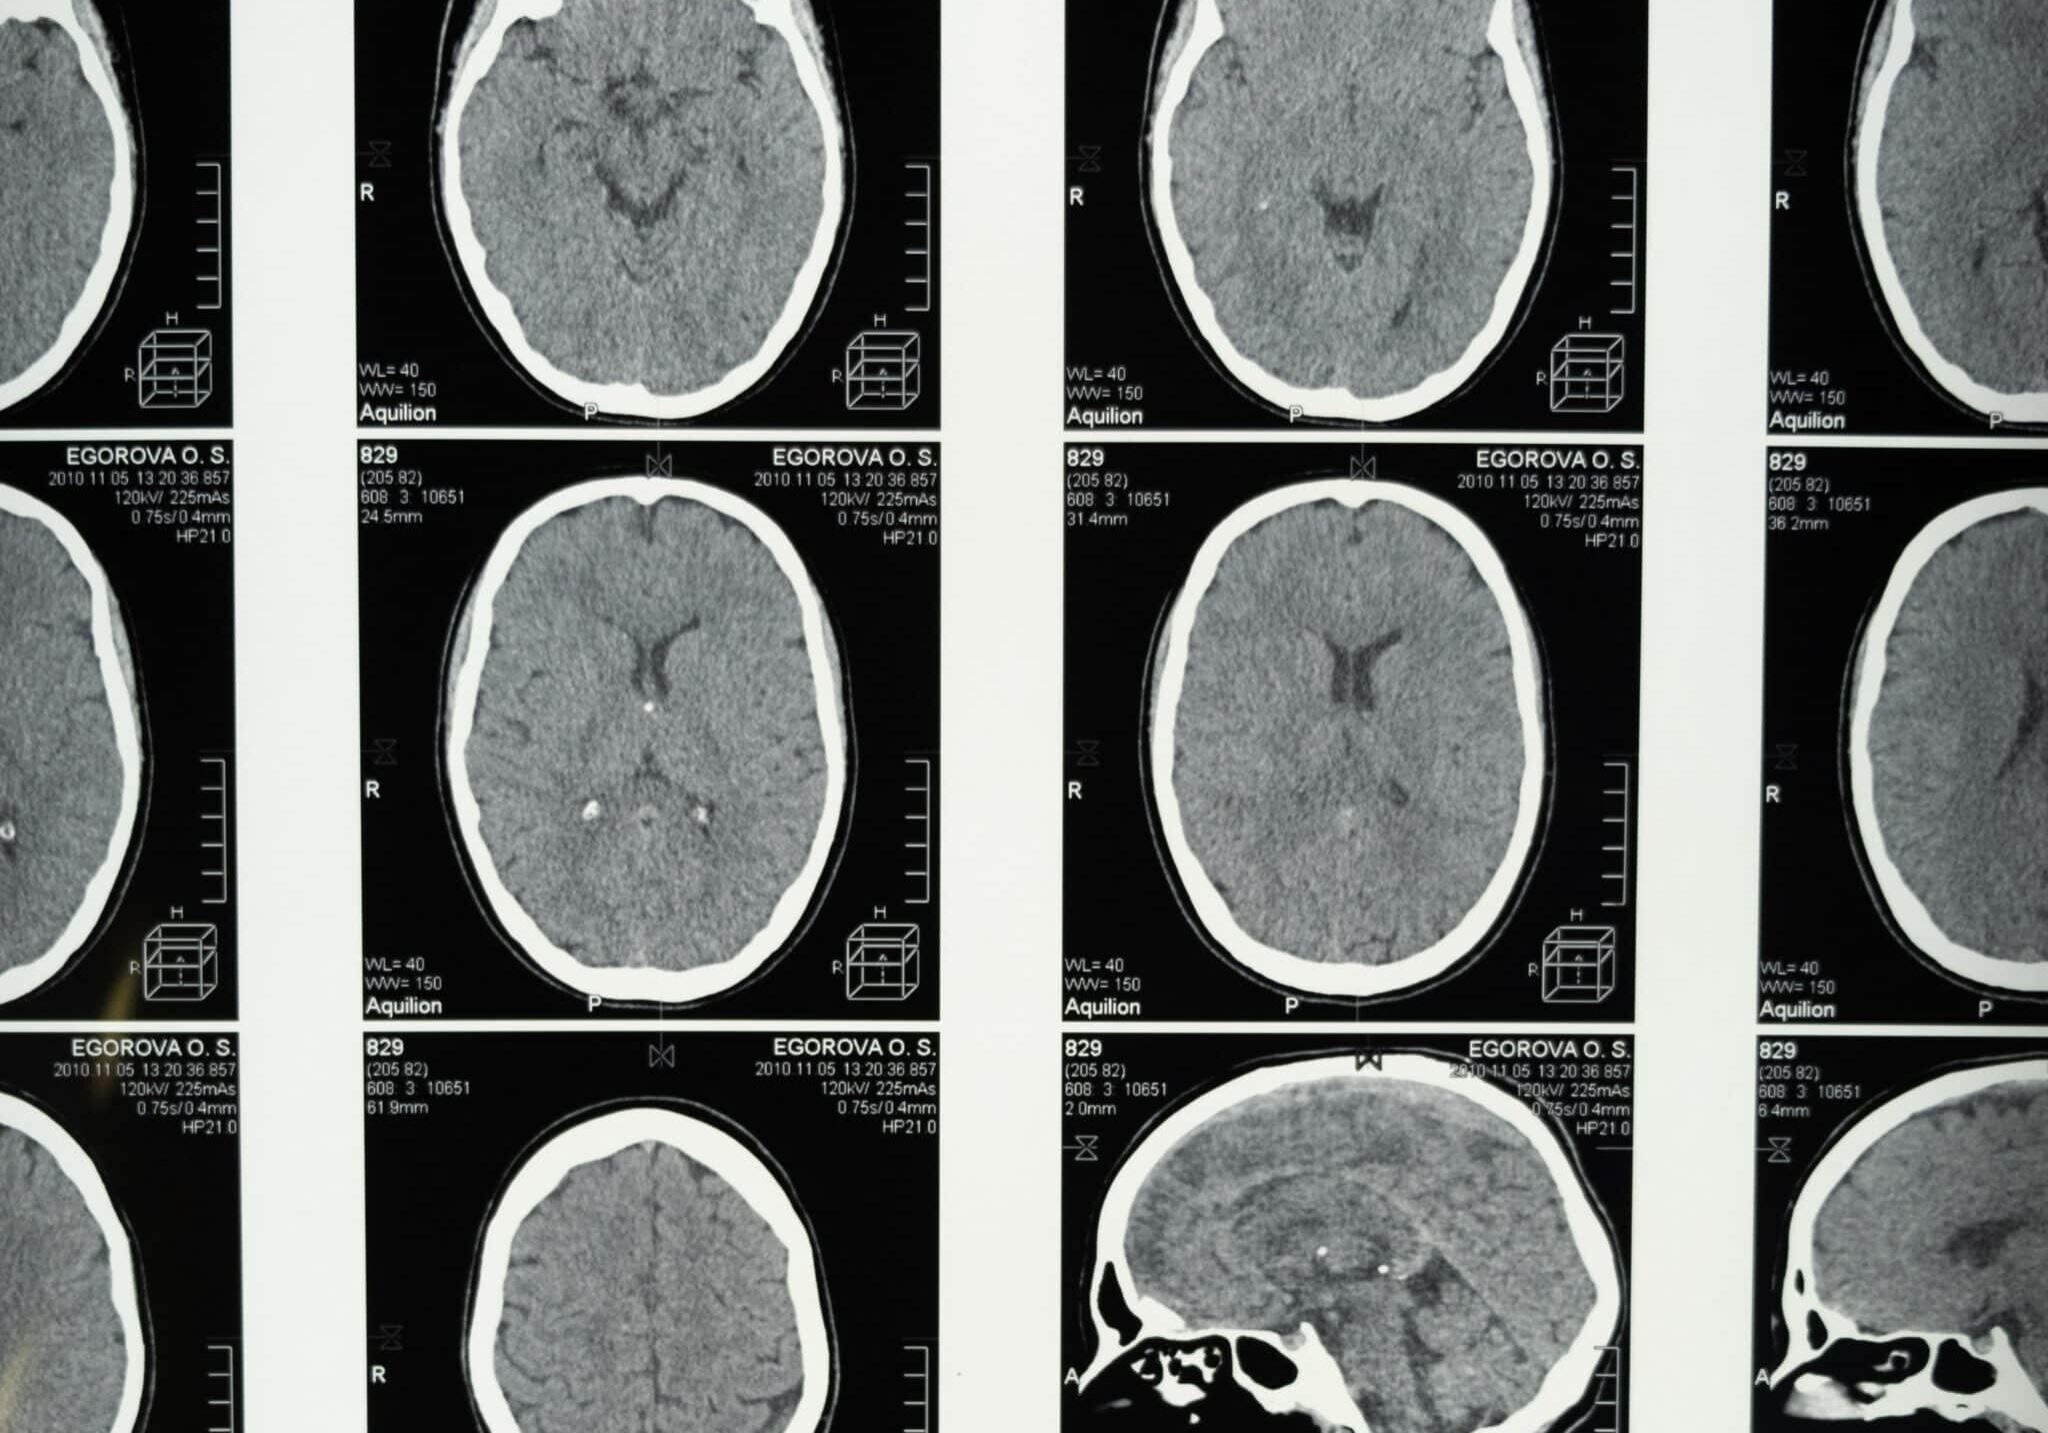

What is Traumatic Brain Injury (TBI)?

TBI is an injury that affects how the brain works. TBI is a major cause of death and disability in the United States. Anyone can experience a TBI, but data suggest that some groups are at greater risk for getting a TBI or having worse health outcomes after the injury.

Brain injury assessment programs offer medical tests to discover the extent of an individual’s injury. These programs also offer treatment and rehabilitation options.

Brain Injury Assessment

Everyday examples of brain injury assessment services can include:

• Connection with a healthcare provider

• Medical exams

• Reading and interpreting exam results

• Diagnosis

• Treatment options